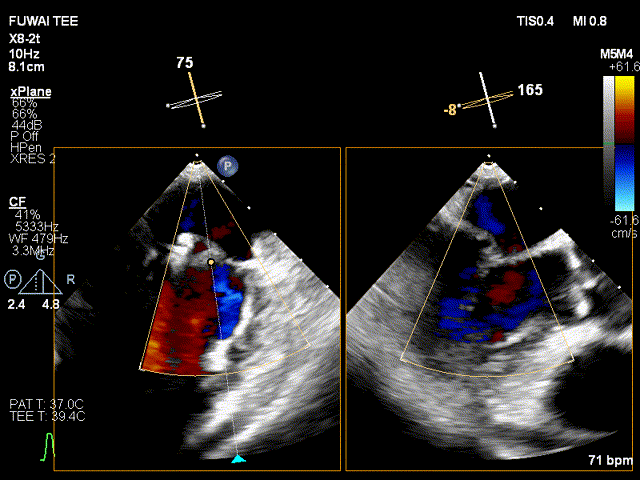

手术团队使用MitraClip®独特的三层双调弯导管,经股静脉穿刺,在食道超声引导下完成房间隔穿刺。穿刺后将导管送入左心房,对准二尖瓣目标位置P2区域。准确捕捉瓣叶,二尖瓣夹释放后,超声显示反流几近消失,患者各项生理指标正常,手术顺利完成。